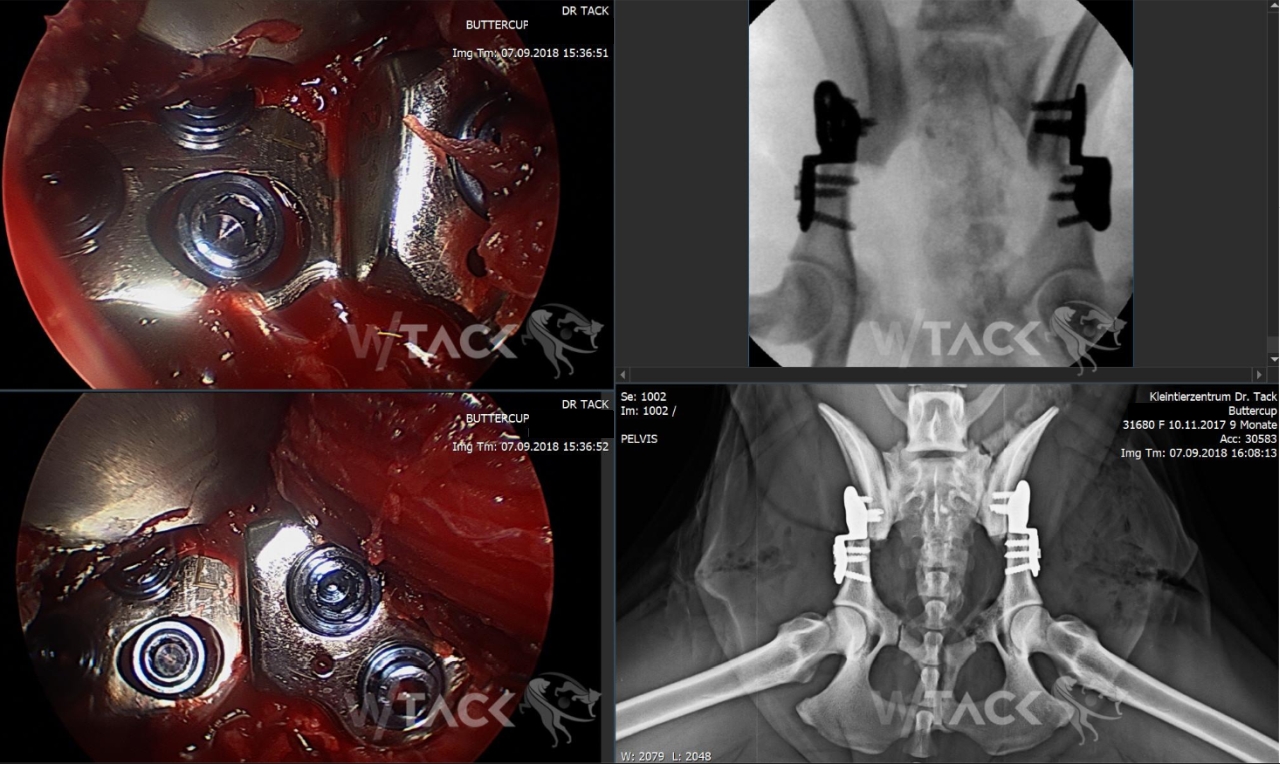

Buttercup – Goldendoodle, 10 Monate, w, 24kg Wegen beidseitiger Hüftgelenksdysplasie führten wir gestern eine beidseitige Pfannenschwenkung (DPO rechts 30°, DPO links 25°) durch.

Buttercup konnte am nächsten Tag nach Hause entlassen werden.

Wir planen eine Röntgenkontrolle in einem Monat.